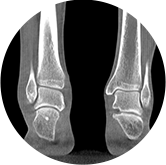

独特的负重位三维影像

填补常规CT/MR空白

助力术前规划和术后评估

• 足踝